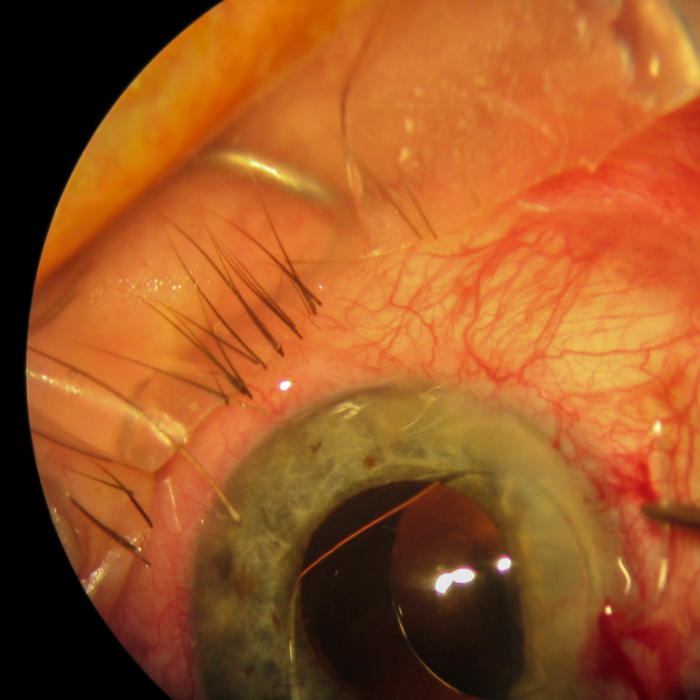

2. Sclerotomia profonda non perforante

Tecnica più moderna e meno invasiva della trabeculectomia.

Il Dr. Lo Schiavo Elia la esegue creando un drenaggio controllato senza aprire completamente la camera anteriore, riducendo il rischio di complicanze post-operatorie.

👉 Vantaggi: minor rischio di infezioni e ipotonia, recupero più rapido.

3. Impianti drenanti (valvole o stent)

In casi complessi o di glaucoma refrattario, si utilizzano microdispositivi filtranti o valvole (Ahmed, Baerveldt, XEN Gel Stent, PreserFlo MicroShunt) che facilitano il deflusso dell’umore acqueo.

👉 Vantaggi: tecnica mini-invasiva, personalizzabile e ripetibile.

👉 Indicata per: glaucomi secondari, post-traumatici o già operati.

4. Chirurgia MIGS (Micro-Invasive Glaucoma Surgery)

Il Dr. Rodolfo Lo Schiavo Elia utilizza anche le più recenti tecniche microchirurgiche mini-invasive, che prevedono l’inserimento di microstent attraverso una piccola incisione corneale.